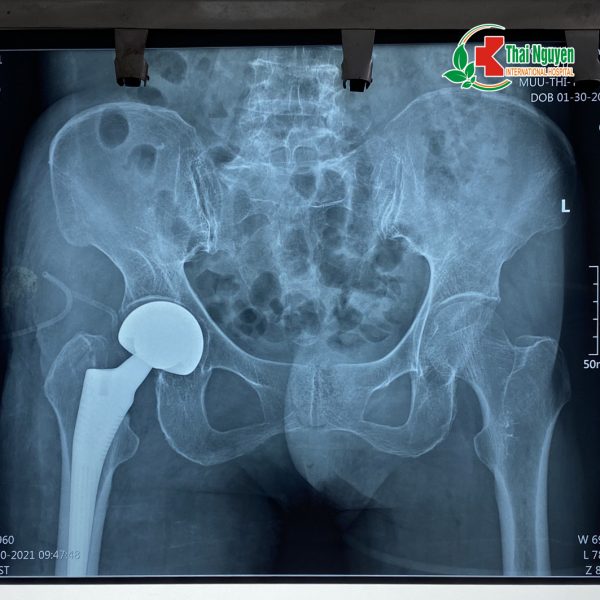

? Trong quá trình phẫu thuật, các bác sĩ đã tiến hành thay khớp háng bán phần cho bệnh nhân. Sau 9 ngày điều trị hậu phẫu tích cực, hiện sức khỏe bệnh nhân đã ổn định, không đau, vận động cảm giác chân tốt, đi lại bình thường.

Hình ảnh chụp Xquang của cụ bà Mưu Thị T sau khi phẫu thuật